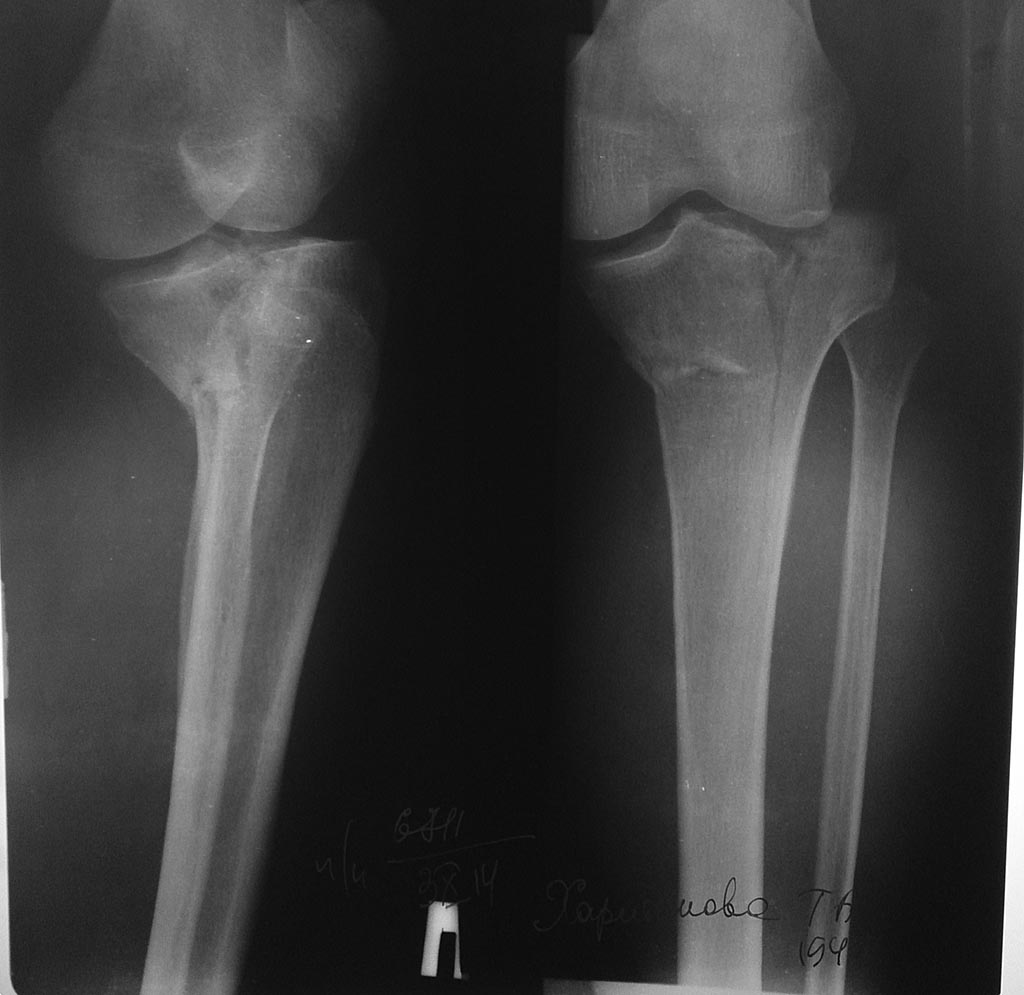

перелом медиального мыщелка большеберцовой кости

Доброго времени суток! Прошу совета. Женщена 66 лет упала с подножки 5 дней назад.

Состояние мягких тканей удовлетворительное. Соматически не отягощена. Посоветуйте, пожалуйста, чем оперировать и из какого доступа. По КТ изолированный перелом мыщелка(часть латерального целая)

А по снимку наружный мыщелок тоже сломан